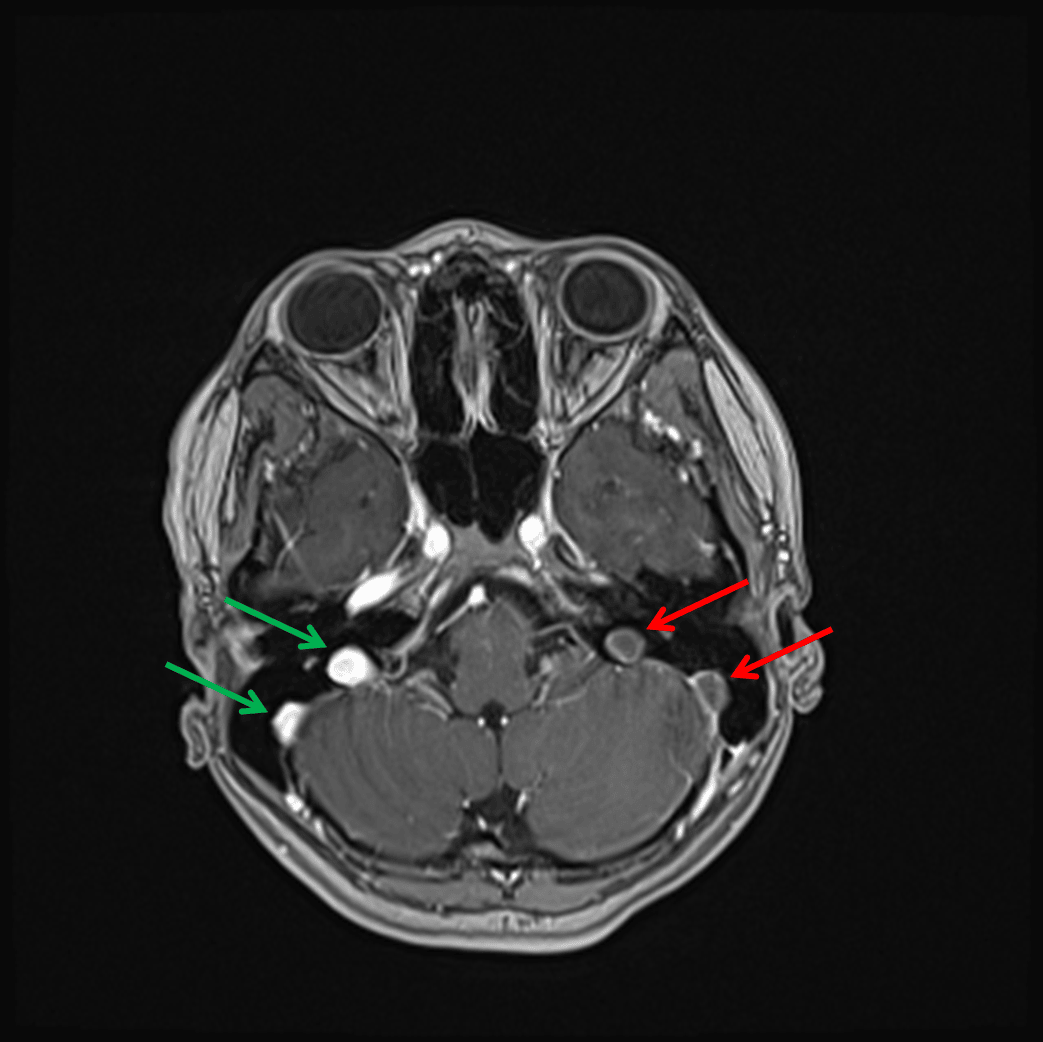

Nonopacification of the left sigmoid sinus and left jugular bulb (red arrows) in contrast to the normally opacified structures on the right (green arrows) on this postcontrast image.